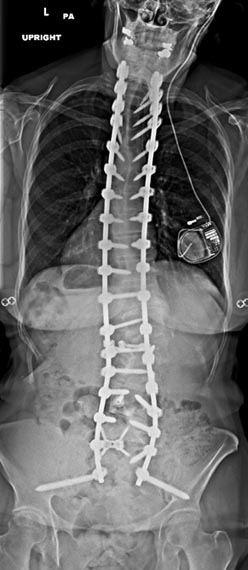

72 year old female who previously had a fusion with another surgeon who developed an infection and underwent multiple surgeries presenting with severe back pain with inability to stand upright.

46 year old woman who previously had Harrington rod spinal fusion from T4 to L3 for idiopathic adolescent scoliosis who presents with back pain and left leg weakness from severe lumbar stenosis distal to her previous fusion.

3 months postop, patient is pain free and weakness completely resolved. She is able to stand upright without pain and improved posture.